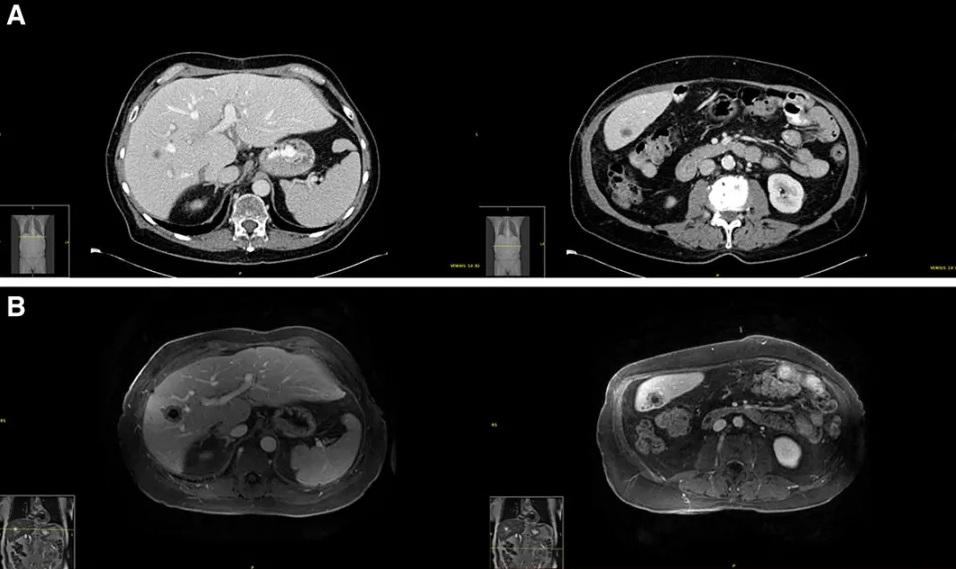

掃瞄檢查發現,69歲男子肝臟出現腫塊,且擴散至全身。(互聯網)